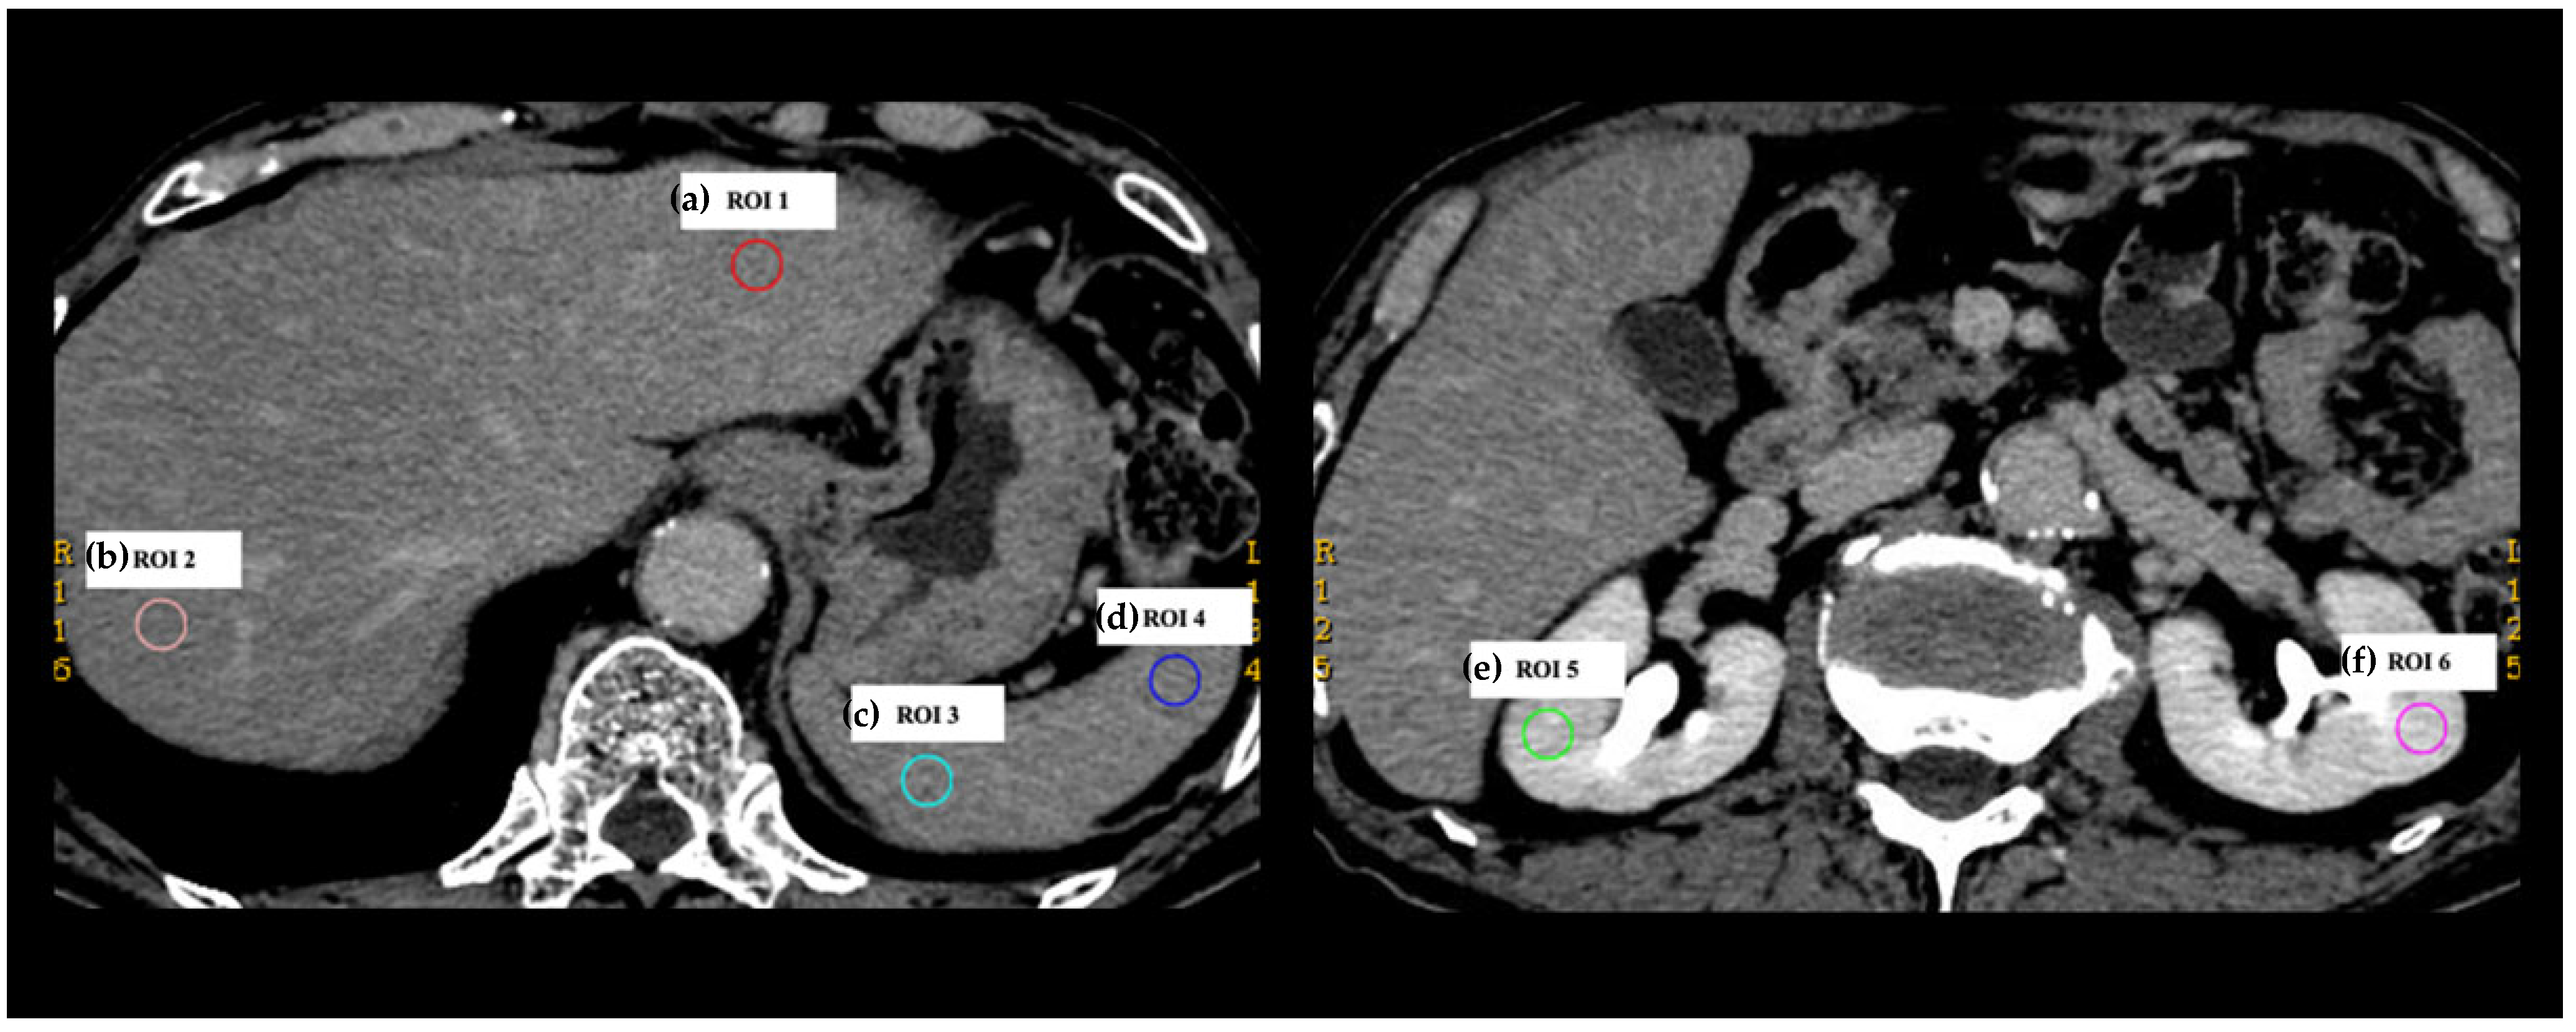

2.3. Collection of DECT Numbers